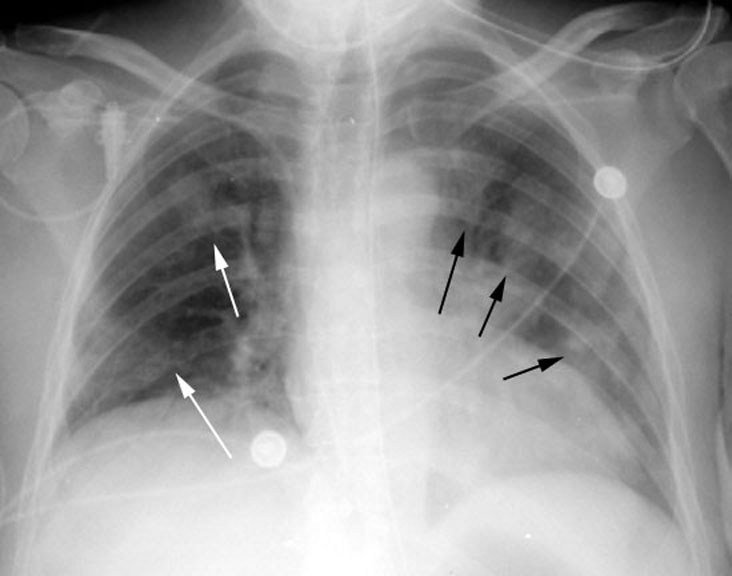

Визуализация и диагностика неинвазивного аспергиллеза с помощью КТ

Раздел: Необычные решения